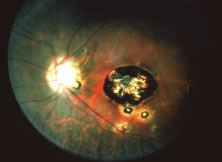

The ARN patient typically presents with progressive visual blurring in one or both eyes occurring over several weeks. These patients often are initially treated with corticosteroids, antitoxoplasmosis drugs, and other medications before arriving at the correct diagnosis. Examination reveals a prominent anterior uveitis that may be granulomatous or nongranulomatous (Fig. 1). Inflammatory signs may be prominent and cause severe pain (Fig. 2). The uveitis may be diffuse and so severe that it causes proptosis. These signs, and the diffuse vitreitis that makes the view of the retina difficult, may contribute to the high degree of delayed and/or misdiagnosis that occurs in the early stages of the disease. Significant vitreous cellular infiltration is seen in the presence of retinitis that is manifest by opacification of the retina, often most prominently in the periphery. Posterior pole involvement may include retinitis, as well as inflammation of the optic nerve head. Optic neuropathy might be the first sign of ARN with subsequent development of other retinal manifestations.8 Ultrasonography and computed tomography (CT) might be helpful in cases of ARN associated with optic nerve edema revealing enlargement of the optic nerve sheath.9 Even in ARN patients who are not immunocompromised and who have no clinical evidence of encephalitis, magnetic resonance imaging of selected cases has shown lesions of the lateral geniculate, optic tracts, and chiasma, which suggests that the virus spreads through the central nervous system (CNS) by axoplasmic transport from the retinal ganglion cells.10 A secondary retinal vasculitis is common, often accompanied by a mild number of retinal hemorrhages. Days to weeks after onset of the infection, the discrete peripheral lesions typically coalesce into a white or yellow ring of infected retina, and the associated vasculature is obliterated (Fig. 3). Necrotic retina desquamates into the vitreous resulting in vitreous sheets.3,6 Eventually, most untreated eyes can be expected to develop retinal detachment resulting from development of multiple full-thickness retinal breaks accompanied by traction or exudation.11 Giant retinal pigment epithelial tears have also been reported.12